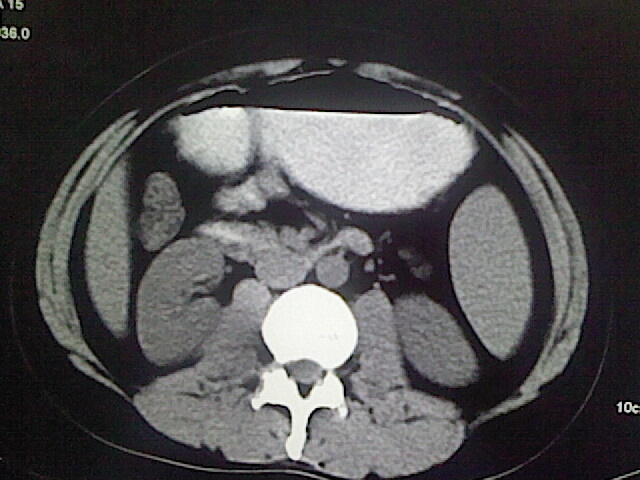

以下是引用卜一在2009-3-14 9:49:00的发言:[br]胆囊萎缩,胆囊壁不规则增厚,内部结构模糊,增强明显强化。另:肝左叶外侧段肝囊肿。支持:慢性胆囊炎!高度可疑:胆囊癌!

以下是引用余辉在2009-3-14 8:48:00的发言:[br]1)慢性胆囊炎。2)肝左叶外侧段肝囊肿。3)脂肪肝。[br]支持,胆囊萎缩,密度增高,不知b超具体有何提示,钙胆汁?结石?

以下是引用jiangjing在2009-3-14 10:18:00的发言:[br]1)慢性胆囊炎。2)肝左叶外侧段肝囊肿。3)脂肪肝。4.】建议行肝功能检查